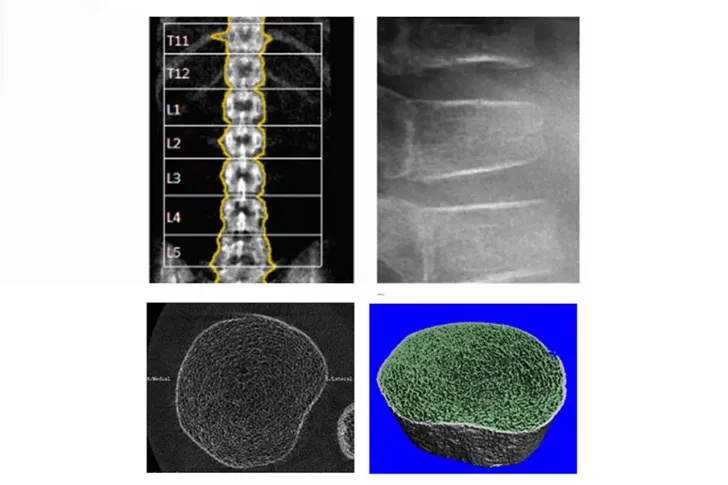

Ziel der Forschung ist es Patientinnen und Patienten mit Diabetes, Insulinresistenzen, Endokrinopathien und Osteoporosen die bestmögliche Behandlung mittels Grundlagen-, klinischer und epidemiologischer Forschung bieten zu können.